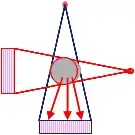

In der Computertomografie werden Absorptionsprofile des Objekts aus vielen Richtungen erstellt und daraus die Volumenstruktur rekonstruiert. Im Gegensatz zum klassischen Röntgen bestehen die gemessenen Daten nicht aus einem zweidimensionalen Bild, sondern sind ein eindimensionales Absorptionsprofil. (In heutigen Geräten werden bei einem Röhrenumlauf jedoch mehrere, bis zu 320 derartige Zeilen ausgelesen.)

Für die Bildentstehung beim Computertomografen ist ein Computer zwingende Voraussetzung, da das Bild nicht wie beim klassischen Röntgenverfahren unmittelbar entsteht, sondern erst aus den gemessenen Daten errechnet werden muss. Für die Berechnung eines CT-Bildes sind Projektionen nötig, die mindestens eine 180°-Rotation um das abzubildende Objekt abdecken.

- Rotate-Rotate-Geräte – Die Röhre muss hier keine translatorische Bewegung mehr durchführen, da ein Fächer von Strahlen ausgesendet wird, welcher den gesamten Bereich durchleuchtet. Sie wird nur noch um den Patienten gedreht, ein auf der gegenüberliegenden Seite des drehenden Teils angebrachtes Kreissegment von Detektorzellen nimmt den Fächer auf. Diese Geräte der dritten Generation kamen im Jahr 1975 auf den Markt und erlaubten erstmals, binnen 20 Sekunden die Daten einer Schicht zu erfassen. Hierdurch war es möglich, den Brust- und Bauchbereich während einer Atemanhaltephase aufzunehmen und damit die bisher unvermeidbaren Atmungsverwischungen zu vermeiden.